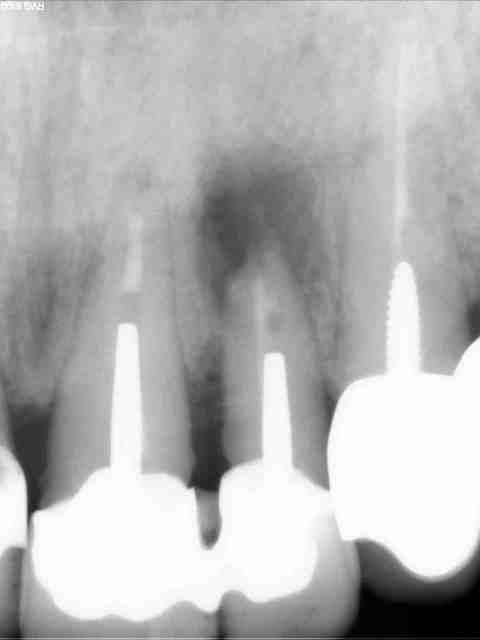

Pas trop nul à chier pour une fois :-)

Obturation a retro au MTA, beta TCP en comblement (plus de corticale osseuse vestibulaire). C'est un choix qui se discute, mais si certains ont des remarques constructives...je prend.

Il me semble que le comblement soit bien fait (j'aurais aussi comblé), mais

il n'y a pas encore de guérison osseuse.

C'est un futur cas d'implant....

1)manque d'étanchéité coronaire

2)ton rapport couronne racine est totalement défavorable heureusement que les ccm sont solidarisées

3)ton atteinte en mésiale remonte plus haut que ta résection.

tu as bien fait de combler pour le clou qui sera peut être à envisager.